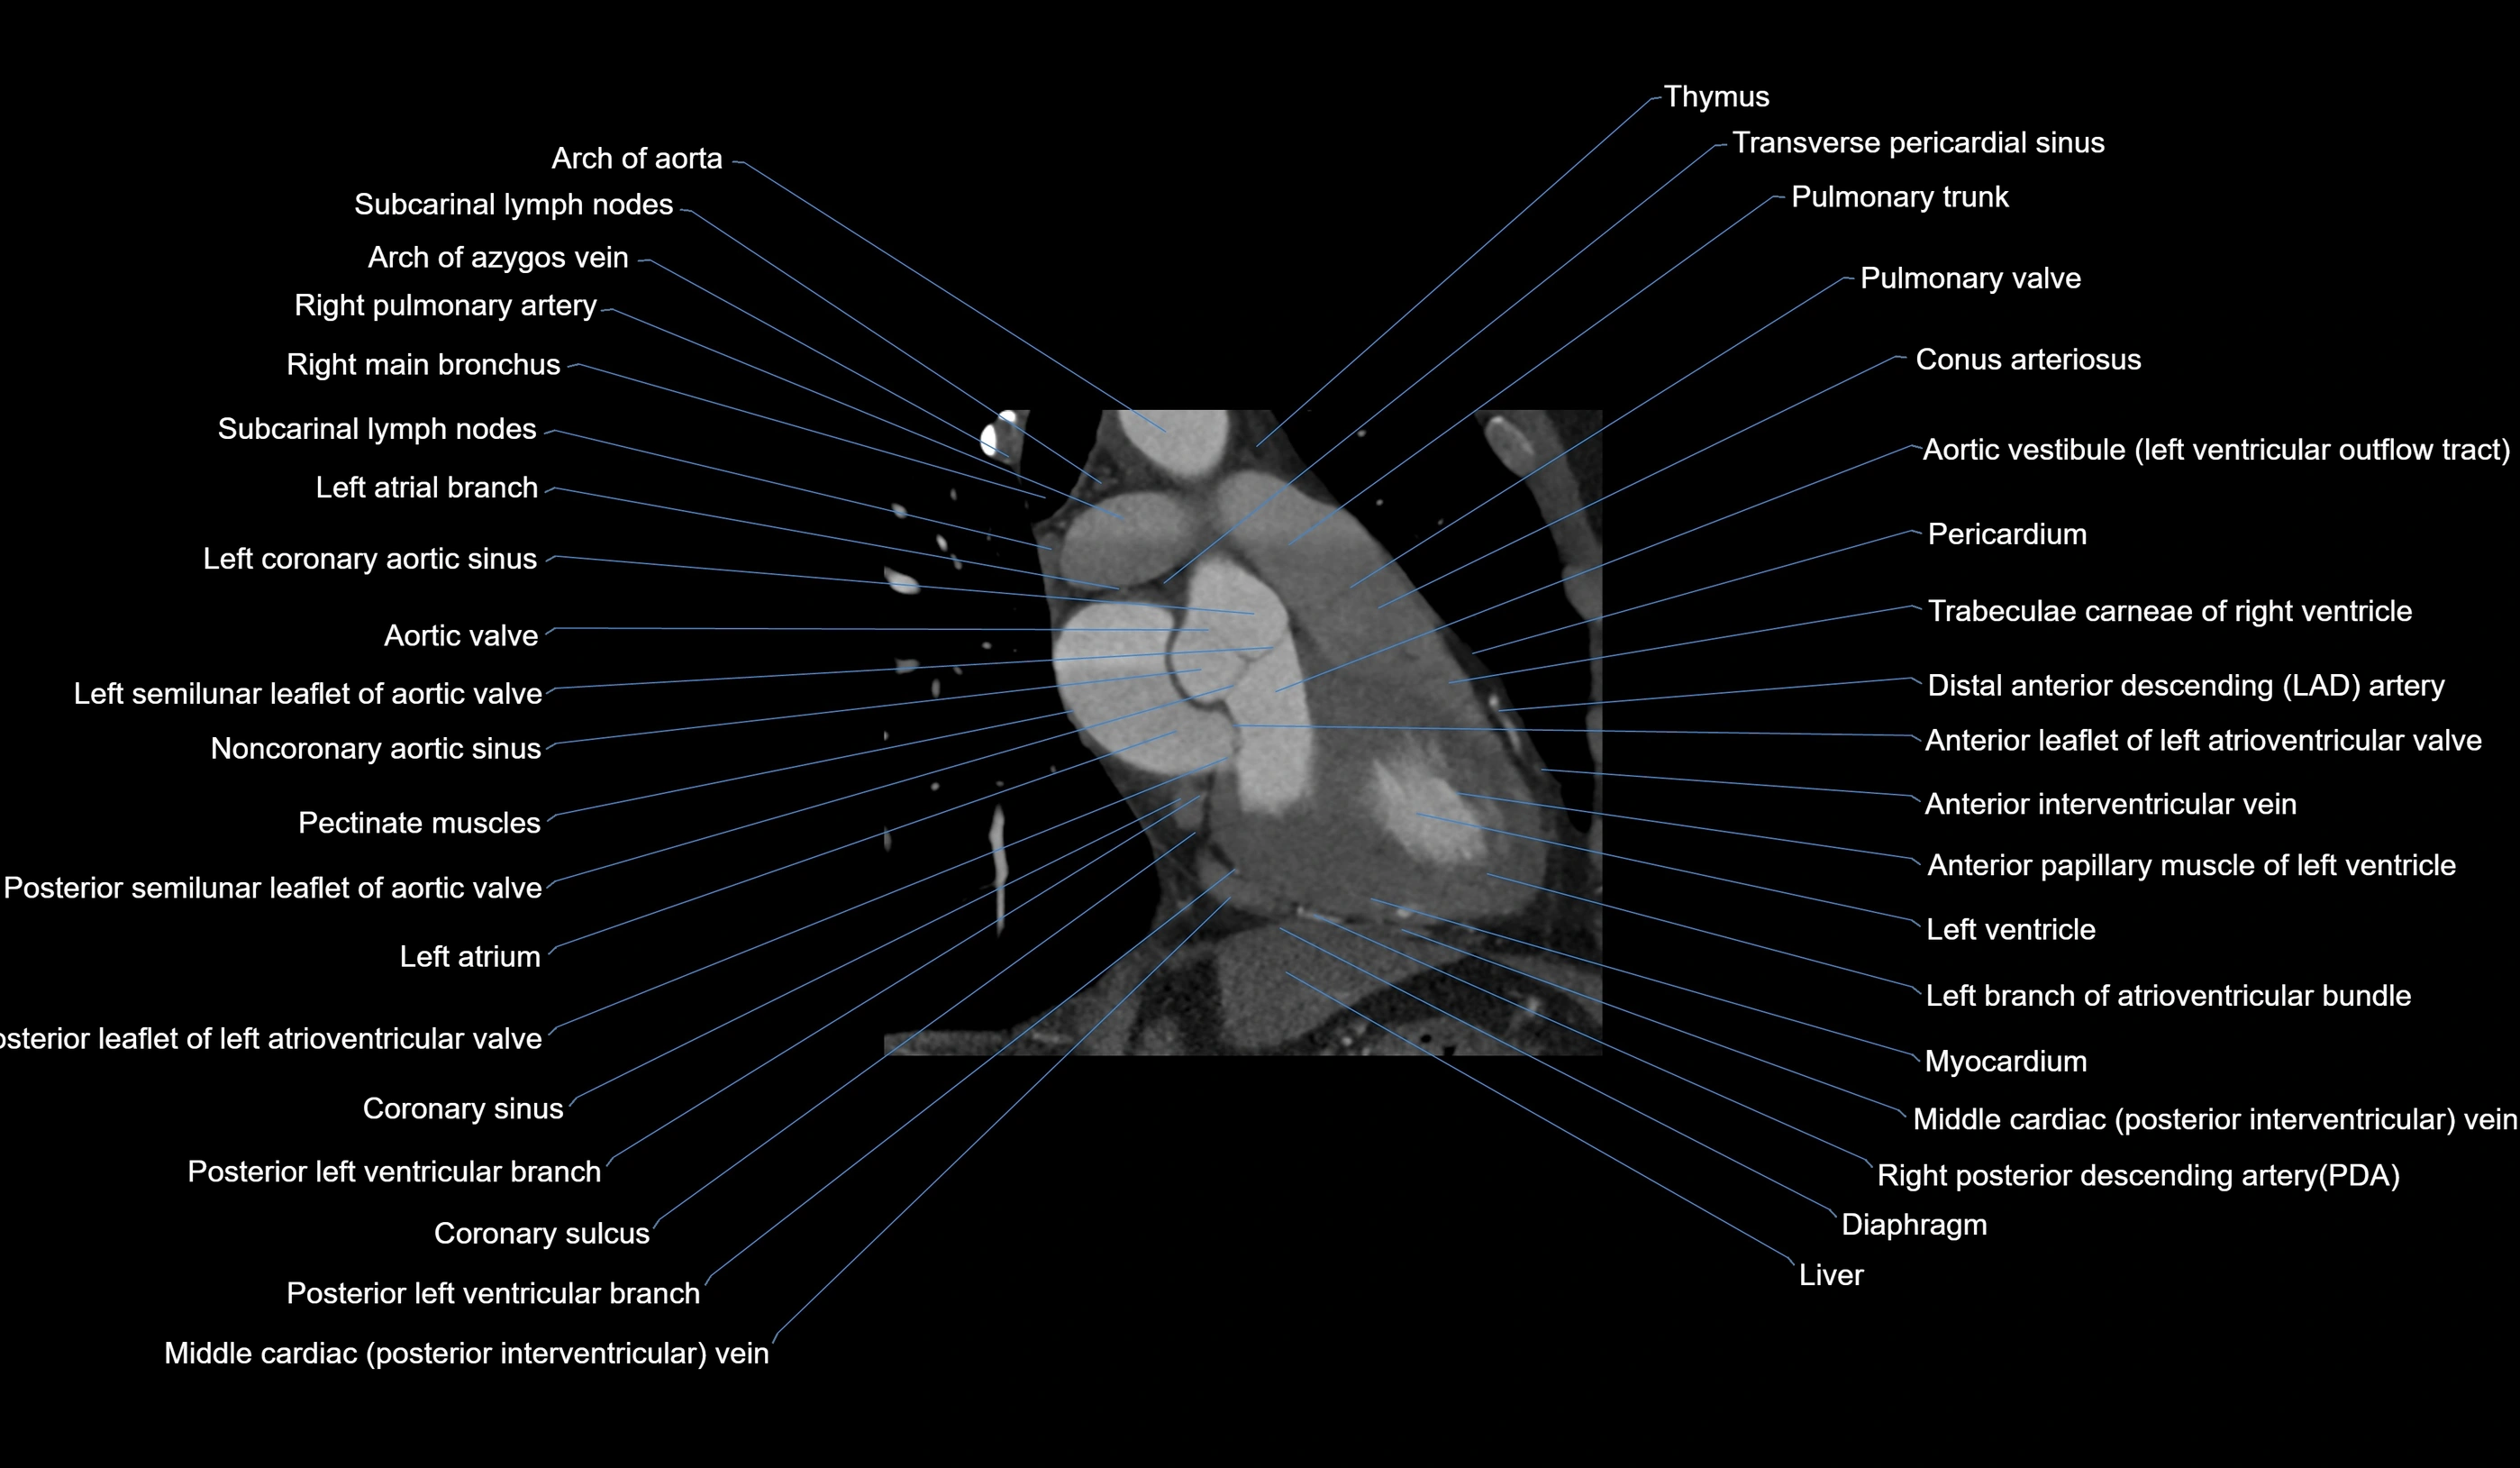

CT Appearance

Non-contrast CT (Calcium Scoring):

-

AM artery visualized for coronary calcium scoring

Calcified plaques appear as hyperdense foci; scored with Agatston method

CT Coronary Angiography (CCTA):

Best non-invasive modality for acute marginal artery visualization

Shows origin, course along the acute margin, and right ventricular branches

Detects stenosis, occlusion, calcified and non-calcified plaques, aneurysm, or anomalous course

Multiplanar reformats and 3D reconstructions help in pre-PCI and surgical planning

Critical for assessing right ventricular infarction risk in RCA disease

MRI image

CT images